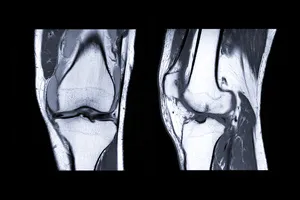

무릎 인공관절수술은 심각하게 손상된 무릎 관절을 인공 관절로 대체하는 수술입니다. 퇴행성 관절염, 외상성 관절염 등으로 인해 무릎 통증이 심하고, 일상생활에 지장을 초래하는 경우, 인공관절 수술을 통해 통증을 완화하고 운동 기능을 회복할 수 있습니다.